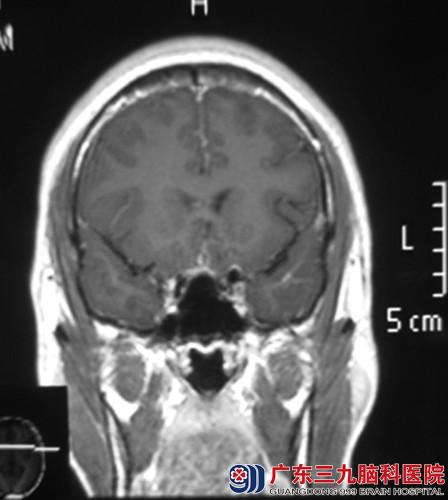

找到广东三九脑科医院综合神经外科 鲁明主任就诊,行头颅MR检查提示:鞍上示一囊实性占位病灶,大小约25.8*18.2*19.9mm,鲁明主任考虑颅咽管瘤可能性大。完善相关检查后,由鲁明主任主刀,在全麻下行经额前纵裂入路颅咽管瘤切除术,术中暴露双侧视神经及视交叉,见肿瘤位于鞍上,呈囊实性,在显微镜下予肿瘤切除,手术顺利结束,术后患者经专科治疗护理,小陈视力、视野正常,未出现任何术后并发症,康复出院。术后病理结果:颅咽管瘤。

术前 术后